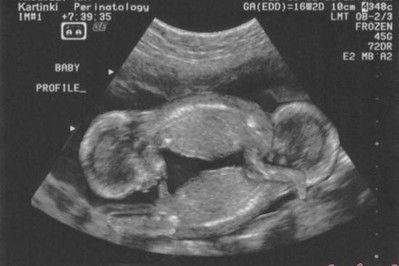

Trafiłam do szpitala na łyżeczkowanie. Dobrze, że taki zabieg trwa tylko chwilę, a pobyt w szpitalu również ogranicza się do kilku godzin, bo umarłabym z tęsknoty z moją córeczką. Była jeszcze wtedy takim okruszkiem. Informacja, którą przekazał mi lekarz po zabiegu była okropna. Okazało się, że nosiłam w sobie jeszcze jednodziecko. Tak, tak... byłam mamą bliźniaków dwu-jajowych. Jeden płód zatrzymał swój rozwój w 3 miesiącu. Miałabym dwójkę maluszków.